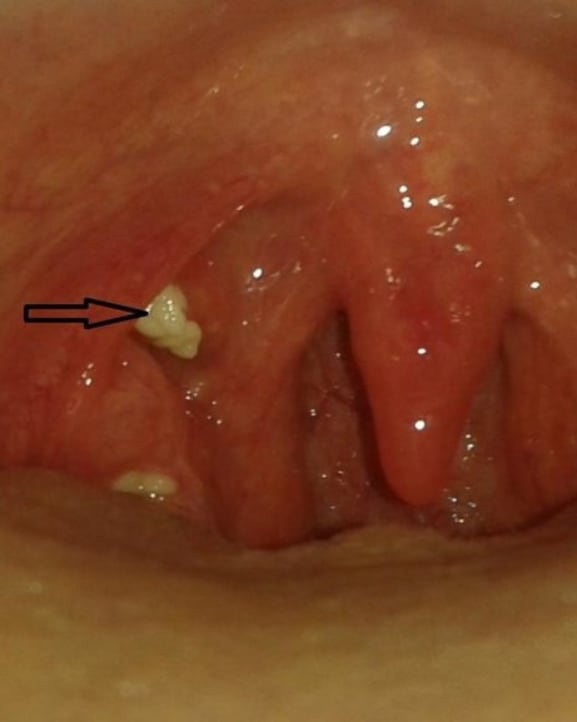

في بعض الحالات يتم إستئصال الحصاة مع اللوزتين، لوجود أعراض مثل ألم بالحلق وعند البلع (وقد يكون ألم رجيع بالأذن) مثل ما حدث مع صاحب الصورة.